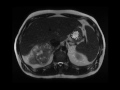

Renal cell carcinoma with renal vein and Inferior Vena Cava (IVC) invasion

MRI images demonstrate an enhancing mass with central necrosis arising from the right kidney with direct invasion into the left renal vein and IVC, found to be clear cell renal cell carcinoma at surgical resection.